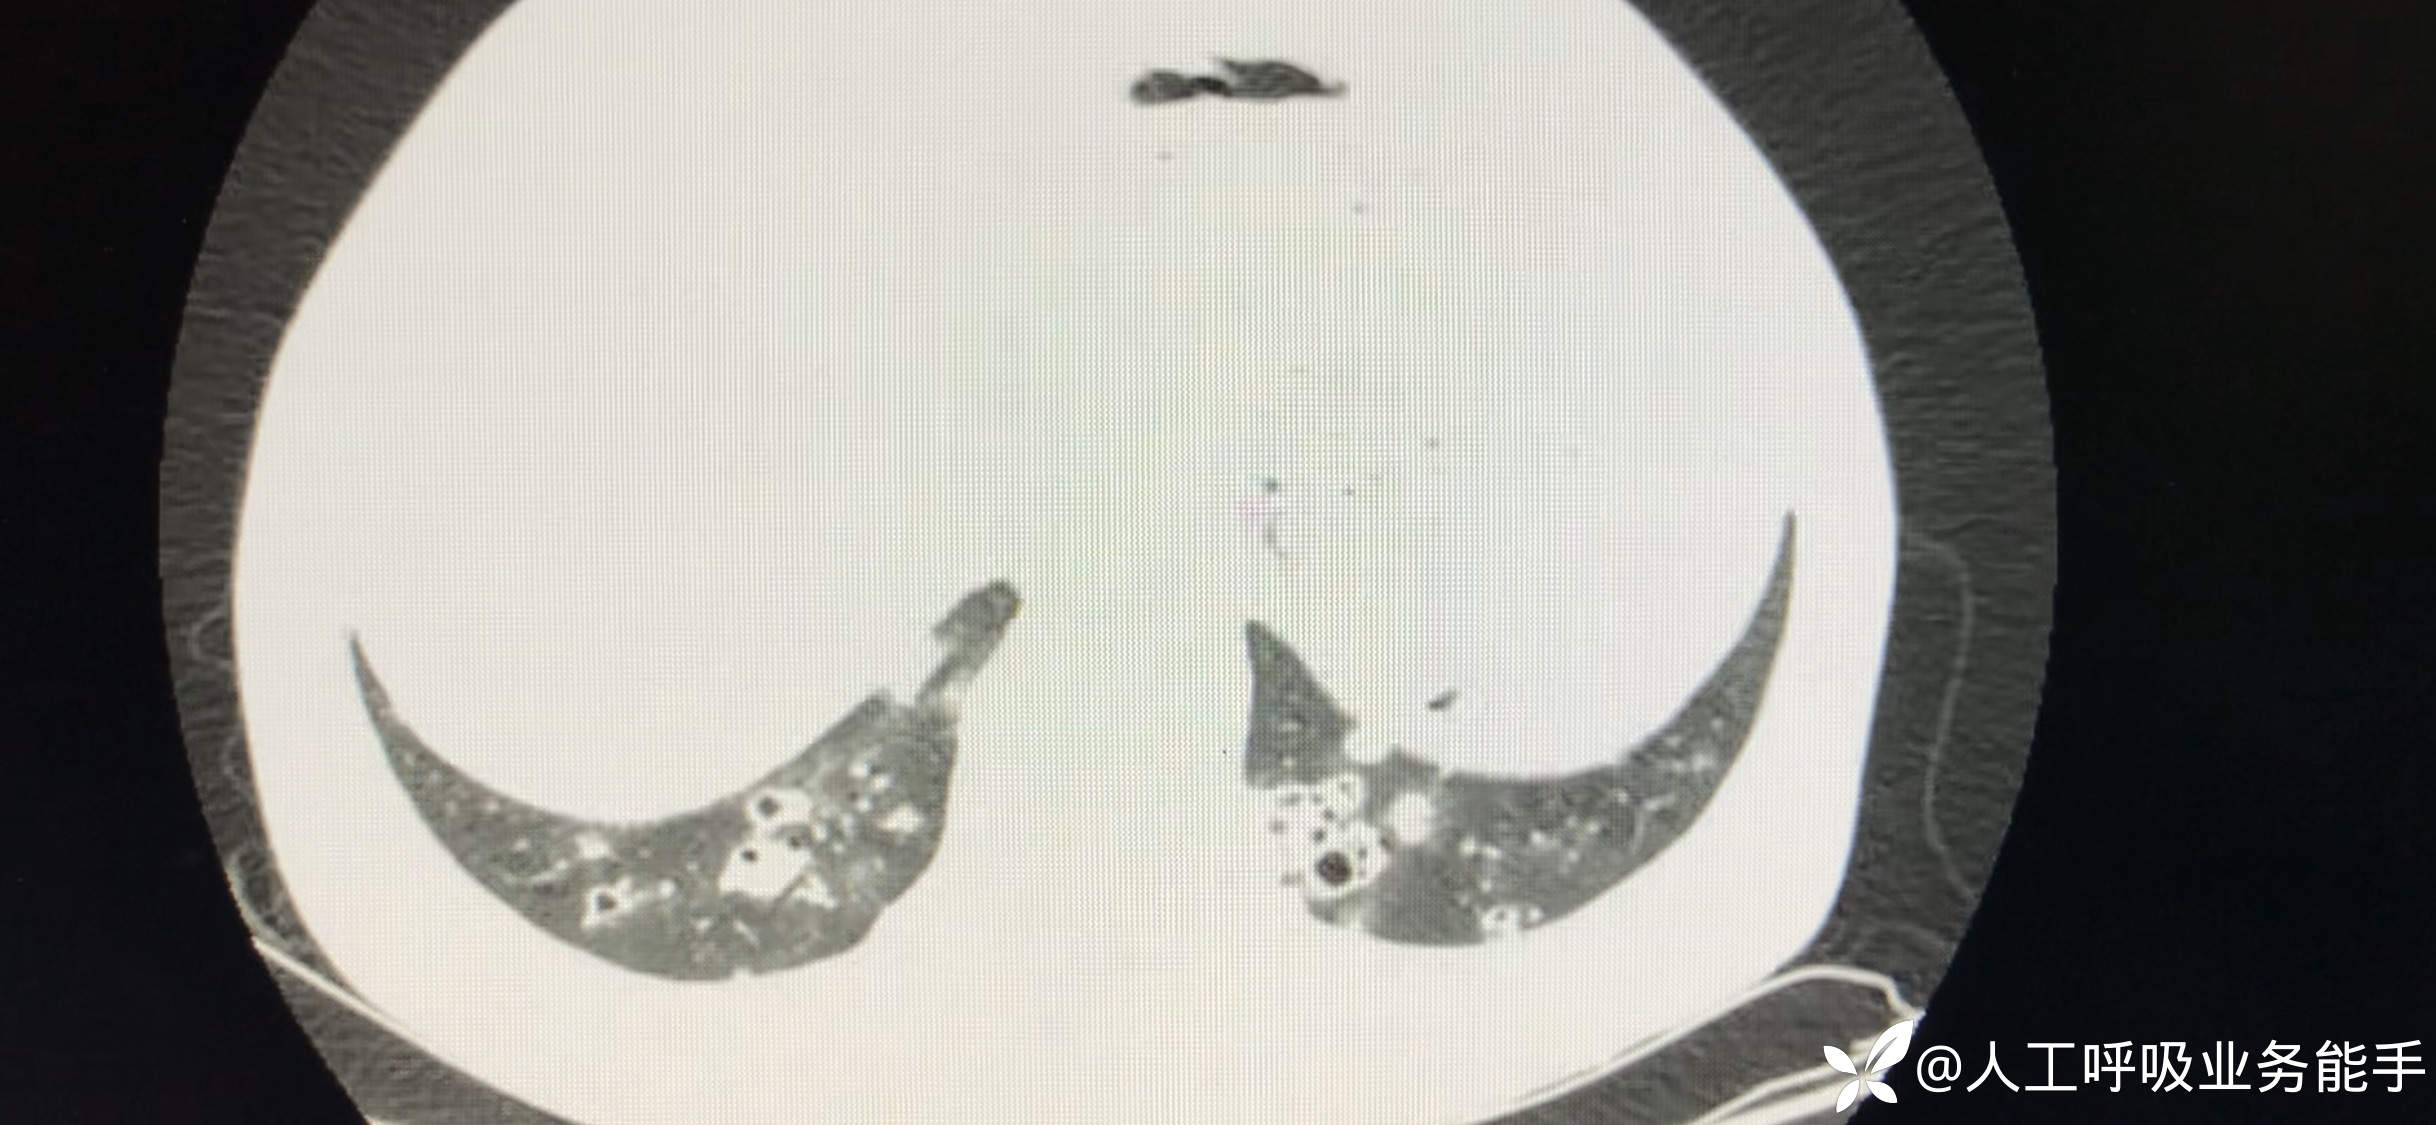

初诊影像:

55岁男性,主诉:咳嗽咳脓痰1周就诊。

1周前上呼吸道感染症状后出现咳嗽、咳痰,无发热,痰液带黑色。1月来乏力,上楼梯时明显,逐渐加重。

既往:不明原因血小板减少3年,最低时8*10⁹/L。近半年使用激素治疗,已经减量至甲泼尼龙4mg qd。否认慢性肺部疾病、糖尿病,从不吸烟。职业:民警。

体格检查:T 36.8°C BP 132/80mmHg HR 78/min RR 18/min SpO2 95%(吸氧5L/min下)神志清楚,双肺呼吸音偏低,未闻及啰音,后背、腹部片状紫癜。余无异常。

血常规和感染标志物:WBC 11.2*10⁹/L PLT 43*10⁹/L N 0.91;CRP 154mg/L,PCT 0.27ng/ml。

肿瘤标志物:NSE 56.3ng/ml(0-16.3)。外周血淋巴细胞亚群:CD4 T细胞 67/uL。T-SPOT 阴性,血清G试验阴性,GM试验阴性,曲霉IgG阴性。